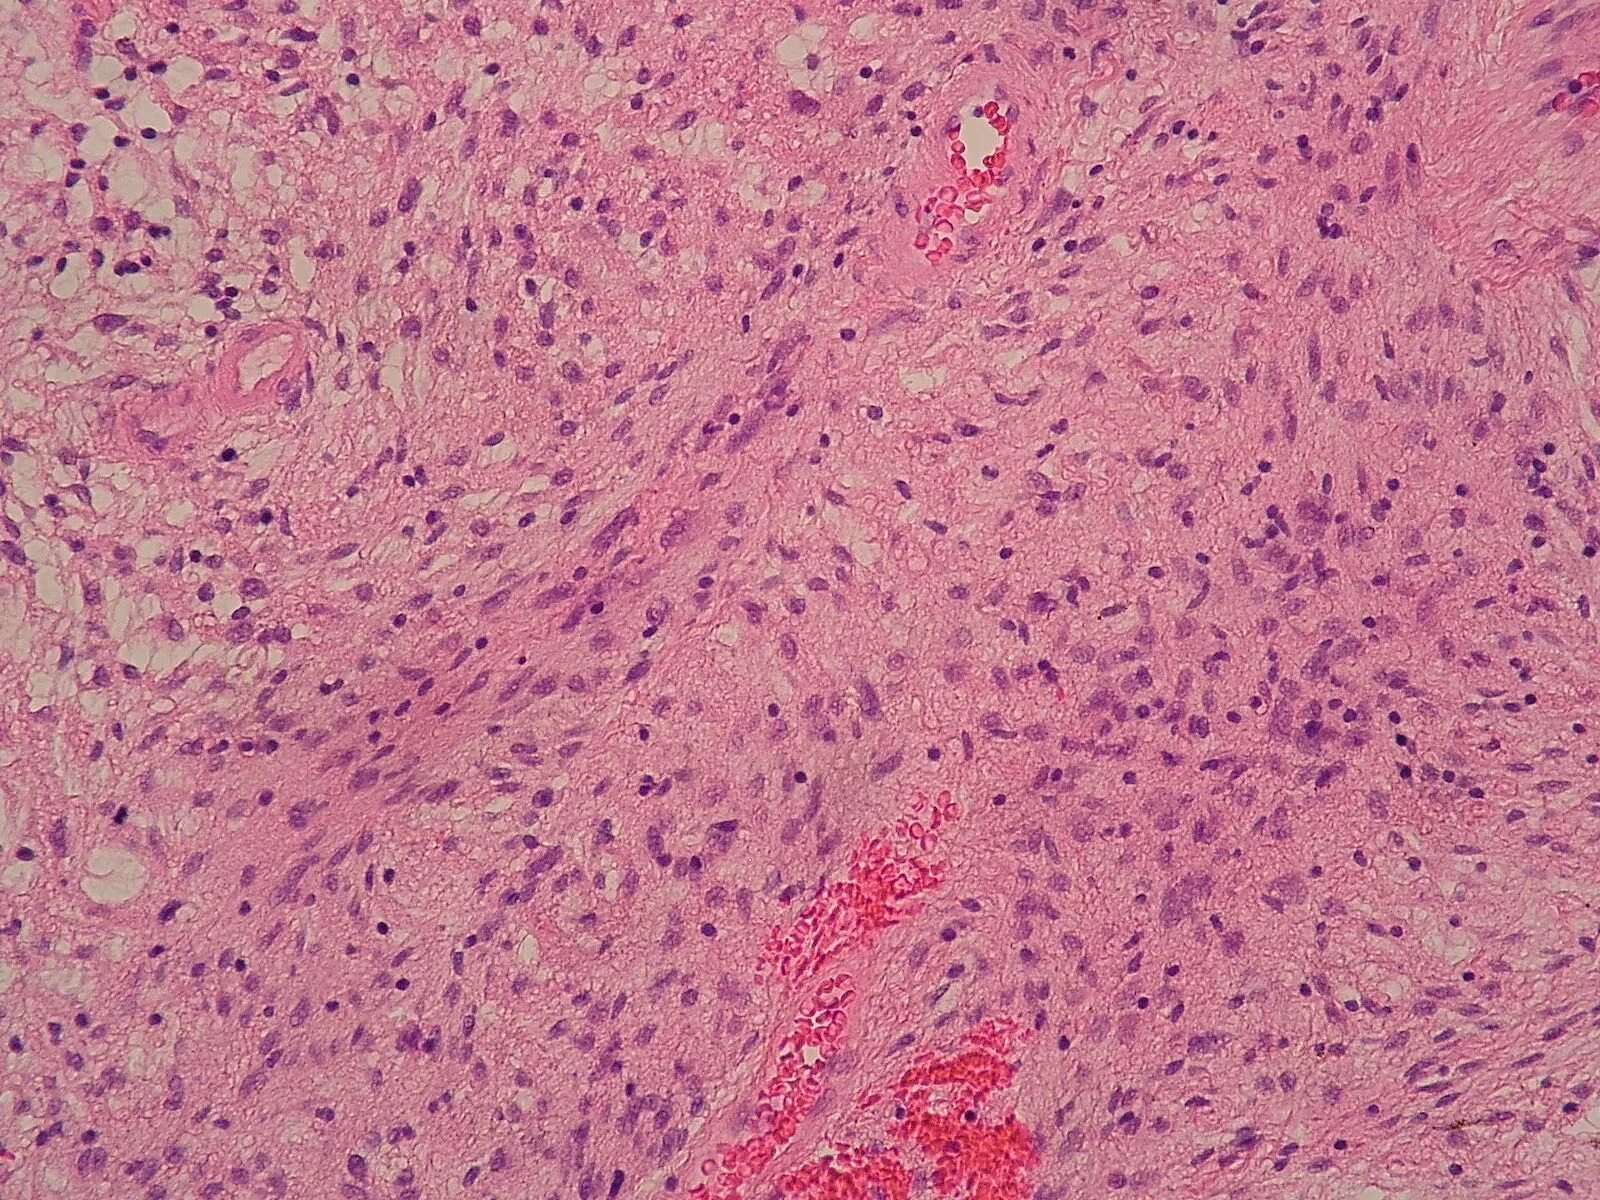

Гистология фото